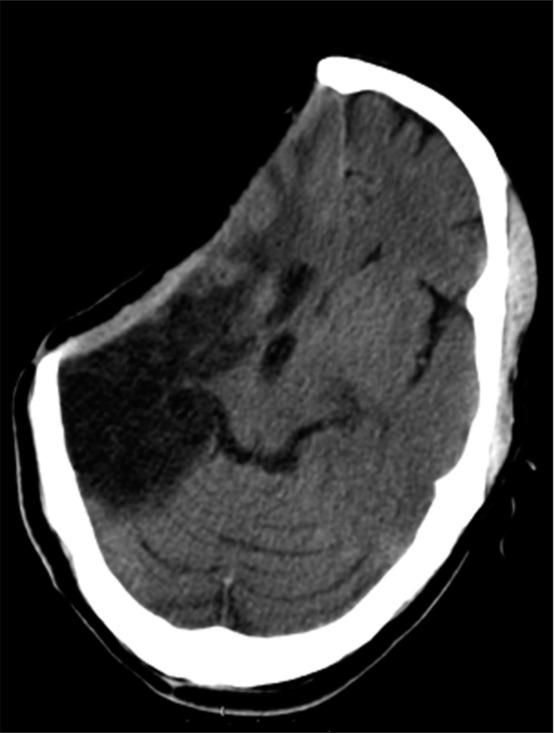

A 52-year-old gentleman with a 210 mL volume and middle cerebral artery territory infarction underwent an emergency craniectomy and 6 months later a titanium mold cranioplasty. Precranioplasty computed tomography (CT) scan evaluation revealed a sunken skin flap with a 9 mm contralateral midline shift. Immediately following an uneventful surgery, the patient had sudden fall in blood pressure to 60/40 mmHg and over a few min had dilated fixed pupils. CT revealed severe diffuse cerebral edema in bilateral hemispheres with microhemorrhages and expansion of the sunken right gliotic brain along with ipsilateral ventricular dilatation. Despite undergoing a contralateral decompressive craniectomy due to the midline shift toward the right, the outcome was fatal.

一名52岁男性,脑梗死体积为210 mL,累及大脑中动脉供血区,接受了急诊颅骨切除术,6个月后进行了钛模颅骨修补术。颅骨修补术前的计算机断层扫描(CT)评估显示皮瓣凹陷,对侧中线移位9 mm。手术顺利完成后,患者血压突然降至60/40 mmHg,几分钟内瞳孔散大固定。CT显示双侧半球严重弥漫性脑水肿,伴有微出血,右侧凹陷的胶质化脑膨出,同侧脑室扩张。尽管因中线向右移位而进行了对侧减压性颅骨切除术,但结果仍为死亡。